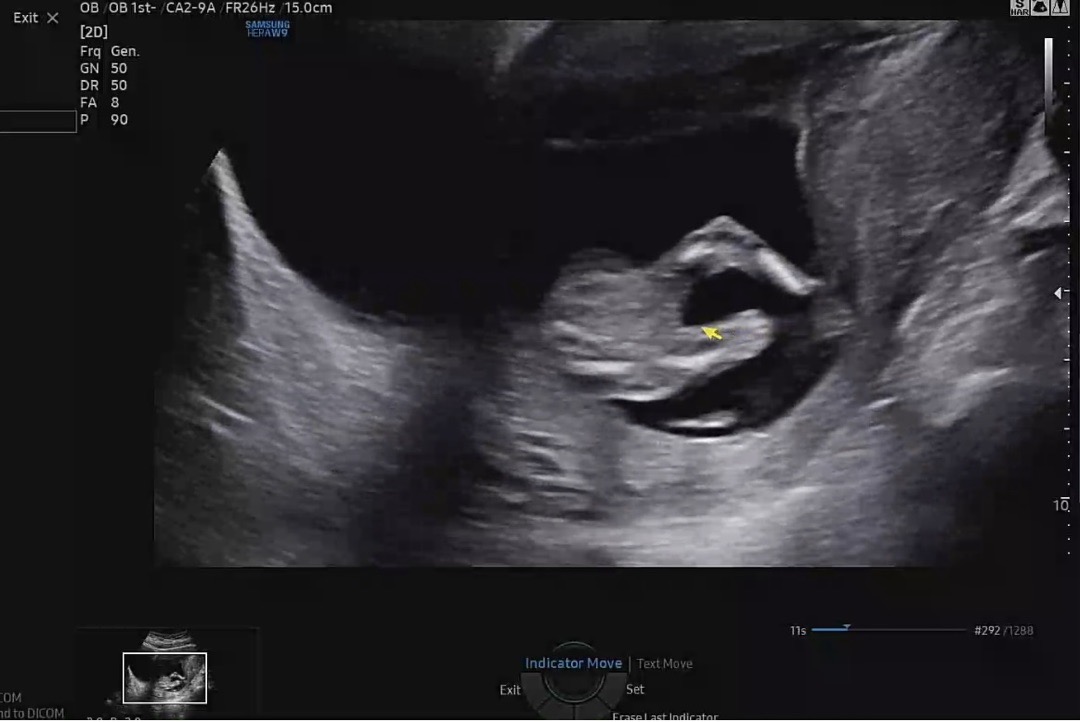

14주 성별 봐주세요

다리쪽 !! 초음파 고수님들,,,🥹 초음파 사진 봐주세요 선생님은 딸 같다 하시는데 정확하지 않아서 🥹